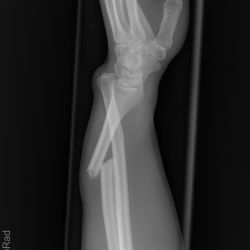

Galeazzi-Fraktur